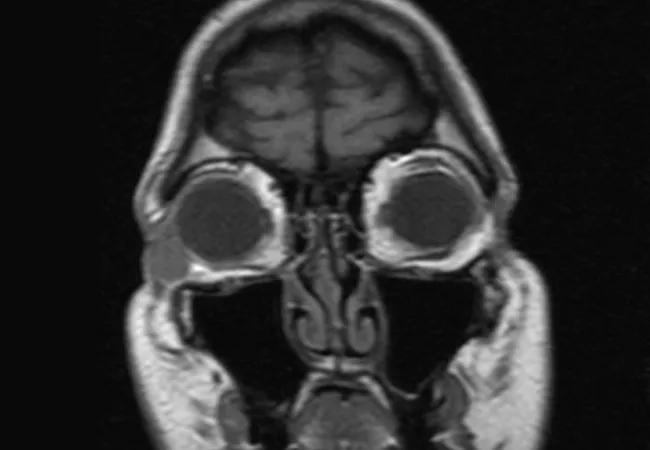

A. External photograph showing inferotemporal orbital nodule B. T1 weighted coronal MRI showing well-circumscribed nodule in the inferotemporal orbit, which is isointense to muscle

B. T1 weighted coronal MRI showing well-circumscribed nodule in the inferotemporal orbit, which is isointense to muscle

Initial evaluation and incisional biopsy at an outside hospital led to the diagnosis of a pleomorphic undifferentiated sarcoma. A 2.2 cm x 2.5 cm round, hard mass was palpated at the inferolateral orbit that was adherent to underlying tissues and separate from the overlying skin (Figure 1A). Proptosis and abnormal extraocular movements were absent. There were no signs of optic disc compression. Orbital magnetic resonance imaging with gadolinium showed a 1.7 cm x 1.0 cm x 1.4 cm homogeneously enhancing subcutaneous mass in the right inferolateral orbit, which was hyperintense on T2 and isointense to muscle on T1, with mild diffusion restriction (Figure 1B). The mass was localized to the preseptal tissues without invasion of the globe, muscles or bone.